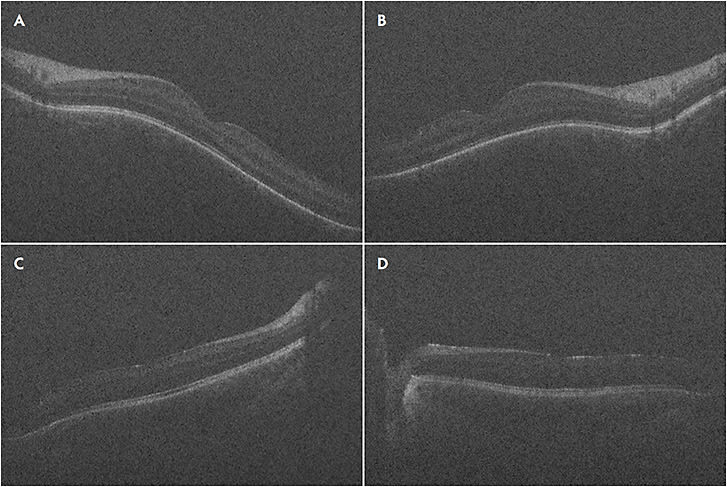

In RD surgery, Mi-iOCT aids in detection of residual subretinal fluid (Figure 4A), small retinal breaks, and proliferative vitreoretinopathy membranes, and it can assist in completion of fluid–air exchange. In TRD surgeries, real-time visualization of the planes may also help achieve more precise delamination and segmentation (Figure 4C).

Lee et al used iOCT to show that residual subretinal fluid is possible even after use of perfluorocarbon liquid in eyes that may appear attached under silicone oil.18 In the DISCOVER trial, surgeons changed their plan intraoperatively when using iOCT in 21% of RD cases with examples including optimal retinotomy sites and distinguishing subretinal hemorrhage from fluid.31,36

Intraoperative OCT has proven helpful in cases of fundus-obscuring vitreous hemorrhage (VH). Intraoperatively, after clearing the hemorrhage, iOCT helps elucidate epiretinal membranes, macular edema, hyaloid traction, and retinal detachment.51 Intraoperative OCT can help ensure carefully manipulating and removing a dropped IOL lying on the retina.52 The video available with this article at retinalphysician.com shows a case of using iOCT to safely remove a dropped IOL off the surface of the macula. Similarly, iOCT can aid in visualizing the resting place during vitrectomy for intra-ocular foreign bodies or subluxed native lens (Figure 4B). Lastly, iOCT was found useful for surgeries with a uveitis-related diagnosis; iOCT provided beneficial feedback in 85% of eyes for fluocinolone acetonide placement and 81% of chorioretinal biopsies, while altering surgical decision making in 38% of chorioretinal biopsies.53

Another area that needs refinement is the light scattering and shadowing that surgical instruments cause on iOCT. This limits visualization of the instrument-tissue manipulations as well as the underlying tissues (Figures 4C and 4D). The amount of shadowing varies depending on instrument material, configuration, thickness, and relative orientation to the optical axis of the OCT.60 Development of instruments that minimize scatter and shadowing will allow for more precise tissue manipulation. Ehlers et al reported use of semitransparent rigid plastic material instruments that allowed decreased light scatter and improved visibility of adjacent tissue as well as the tissue immediately underlying the instruments.61 Furthermore, development of new software algorithms may assist in software-based processing of the image to minimize shadowing, as well as localize and track the beam to the area of interest to minimize manual readjustments.